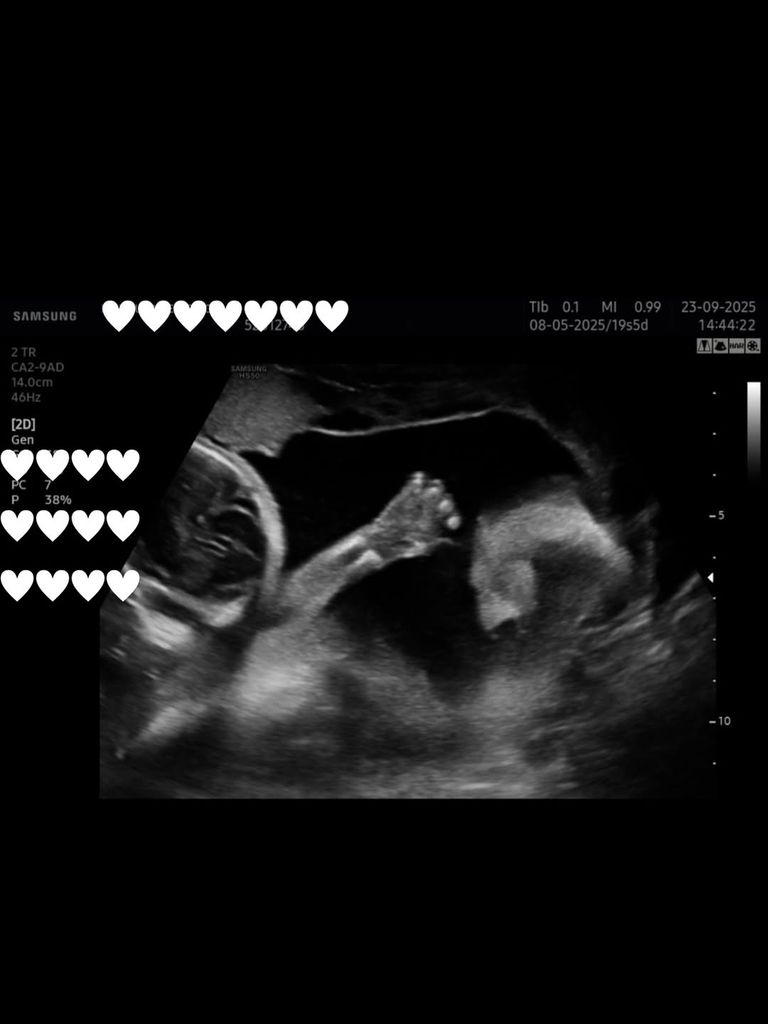

Este duro golpe llega en uno de los momentos más especiales para la pareja. Estela Grande anunció recientemente su embarazo con un emotivo vídeo en blanco y negro en el que se escuchaba el latido de sus dos bebés durante una ecografía. “Vamos a ser papás, dos vidas que llegan para hacernos más grandes, más fuertes, más uno”, escribió entonces la modelo, que no podía ocultar su felicidad.